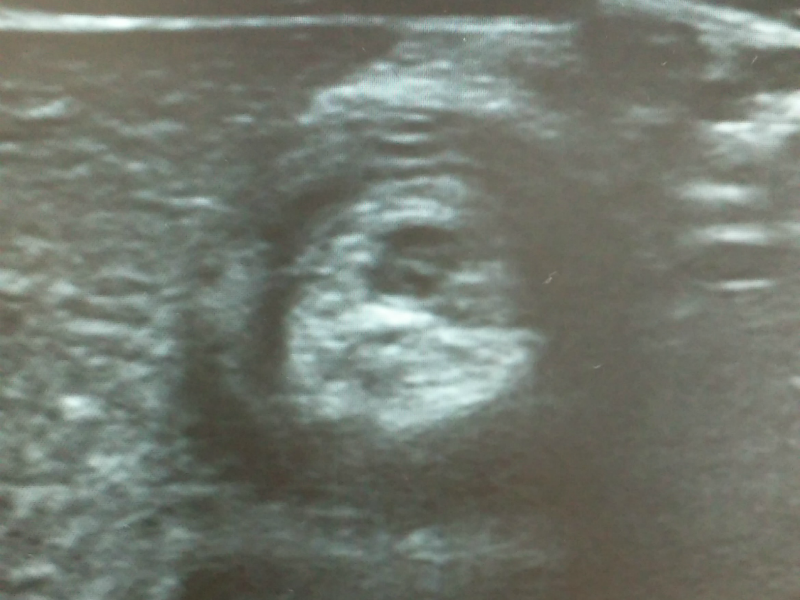

이 질환은 대부분 6개월에서 2세 사이 건강한 소아에서 갑자기 발생합니다. 보통 심하게 자지러지는 복통이 5~10분 간격으로 반복적으로 나타나는 경우가 흔하고 시간이 지나면 구토와 혈변, 그리고 젤리 같은 변을 보는 특징이 있습니다. 장벽에 있는 점액질이 함께 나오는 것이겠죠. 진단은 초음파로 장이 겹쳐져 막힌 부분을 확인하는 것이고 치료는 항문을 통해 공기나 조영 물질을 섞은 액체로 장을 밀어내어 펴주는 치료를 하게 됩니다. 간혹 관장 정복에 실패하거나 장천공이 발생하면 수술적 치료가 필요한 경우도 생깁니다.

혈변을 확인하자마자 급히 달려간 대학병원 응급실에서 다행히 장중첩증 진단과 치료를 잘 마칠 수 있었습니다. 정복을 마치고 보는 첫 변에서 혈흔이 약간 비치긴 하지만 정상변에 가까운 변을 보는 게 어찌나 반갑던지요. 평소 아이보다 보면 힘들 때가 많지만 역시 잘 먹고 잘 자고 잘 싸는 게 이렇게 행복하고 감사한 거구나, 새삼 느낍니다.